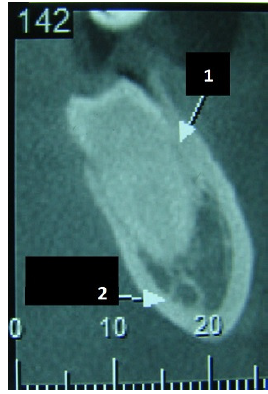

Observando a imagem abaixo, marque a alternativa que corresponde ao diagnóstico radiográfico (seta 2 ):

Odontoma.

Fibroma Ossificante.

Canal Mandibular.

Glândula Submandibular.

Abcesso Periapical.